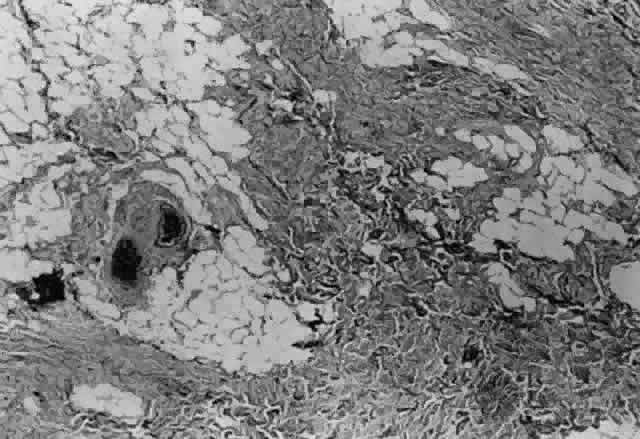

After the incision has been made and the dissection through Tenon's capsule has been completed to the surface of the sclera, muscle hooks are passed behind the rectus muscle to identify the insertion of the muscle. Once the muscle has been “hooked,” there is improved control of the globe. This will facilitate the blunt and sharp dissection that will be needed to reflect the conjunctiva over the tendon of the muscle (Fig. 15). Sharp dissection beneath the conjunctiva is used to separate fibrous tissue and restrictive bands from the surface of the muscle capsule and the sclera (Figs. 16 and 17). Frequently it will be necessary to remove small amounts of tissue to visualize the area of contact of the muscle insertion (Fig. 18).

Fig. 18. This fibrous tissue was removed from a patient with prior strabismus surgery. Note the connective tissue component. Thick bands of compact collagenous scar tissue infiltrate orbital fat (hematoxylin and eosin, X 100). (Courtesy of Bruce L. Johnson, MD)

Once the muscle insertion has been “cleaned” of adherent tissue, the distance the muscle is from the original insertion and from the limbus is measured and recorded (Figs. 19 and 20).